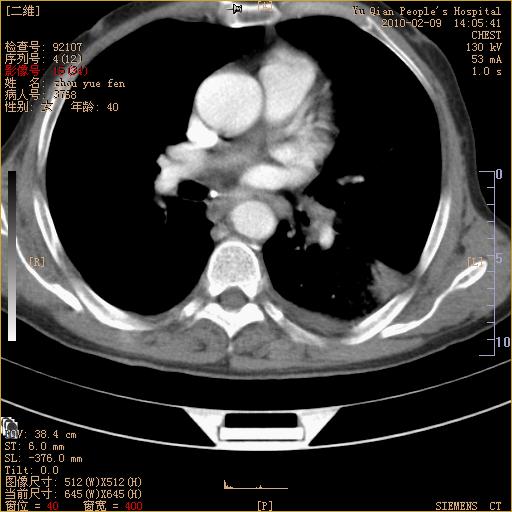

男性,73岁,咳嗽咳血数天,诊为肺ca伴左肺下叶后段阻塞性炎症、肺不张妥否?

右下肺有转移?

左下肺中央型肺癌伴结段形肺不张,左侧胸腔积液,纵隔内见部分增大淋巴结(反应性增生或转移)

左下基底干支气管明显变窄。

左肺下叶基底段支气管狭窄,左肺门增大,左肺下叶团片状病灶。中心型肺癌伴柱塞性炎症可能大,建议支气管镜检查。

左下肺中央型肺癌伴节段性肺不张,左侧胸腔积液,纵隔内见肿大淋巴结

左下基底段支气管变窄。建议进一步纤支镜检查。

1、左肺下叶后基地段肺癌伴阻塞性炎症,左下肺门淋巴结转移。2、左侧胸腔积液。